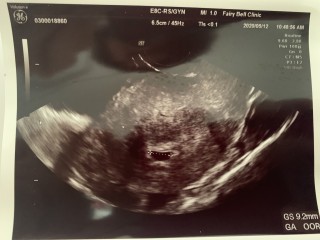

写真:5w5d:ゆーちゃんさん

昨日から少し出血があり急遽病院に行ってきました。

8ミリから19.8ミリまで成長していました。卵黄嚢も見えました。

来週には心拍確認できるかな?